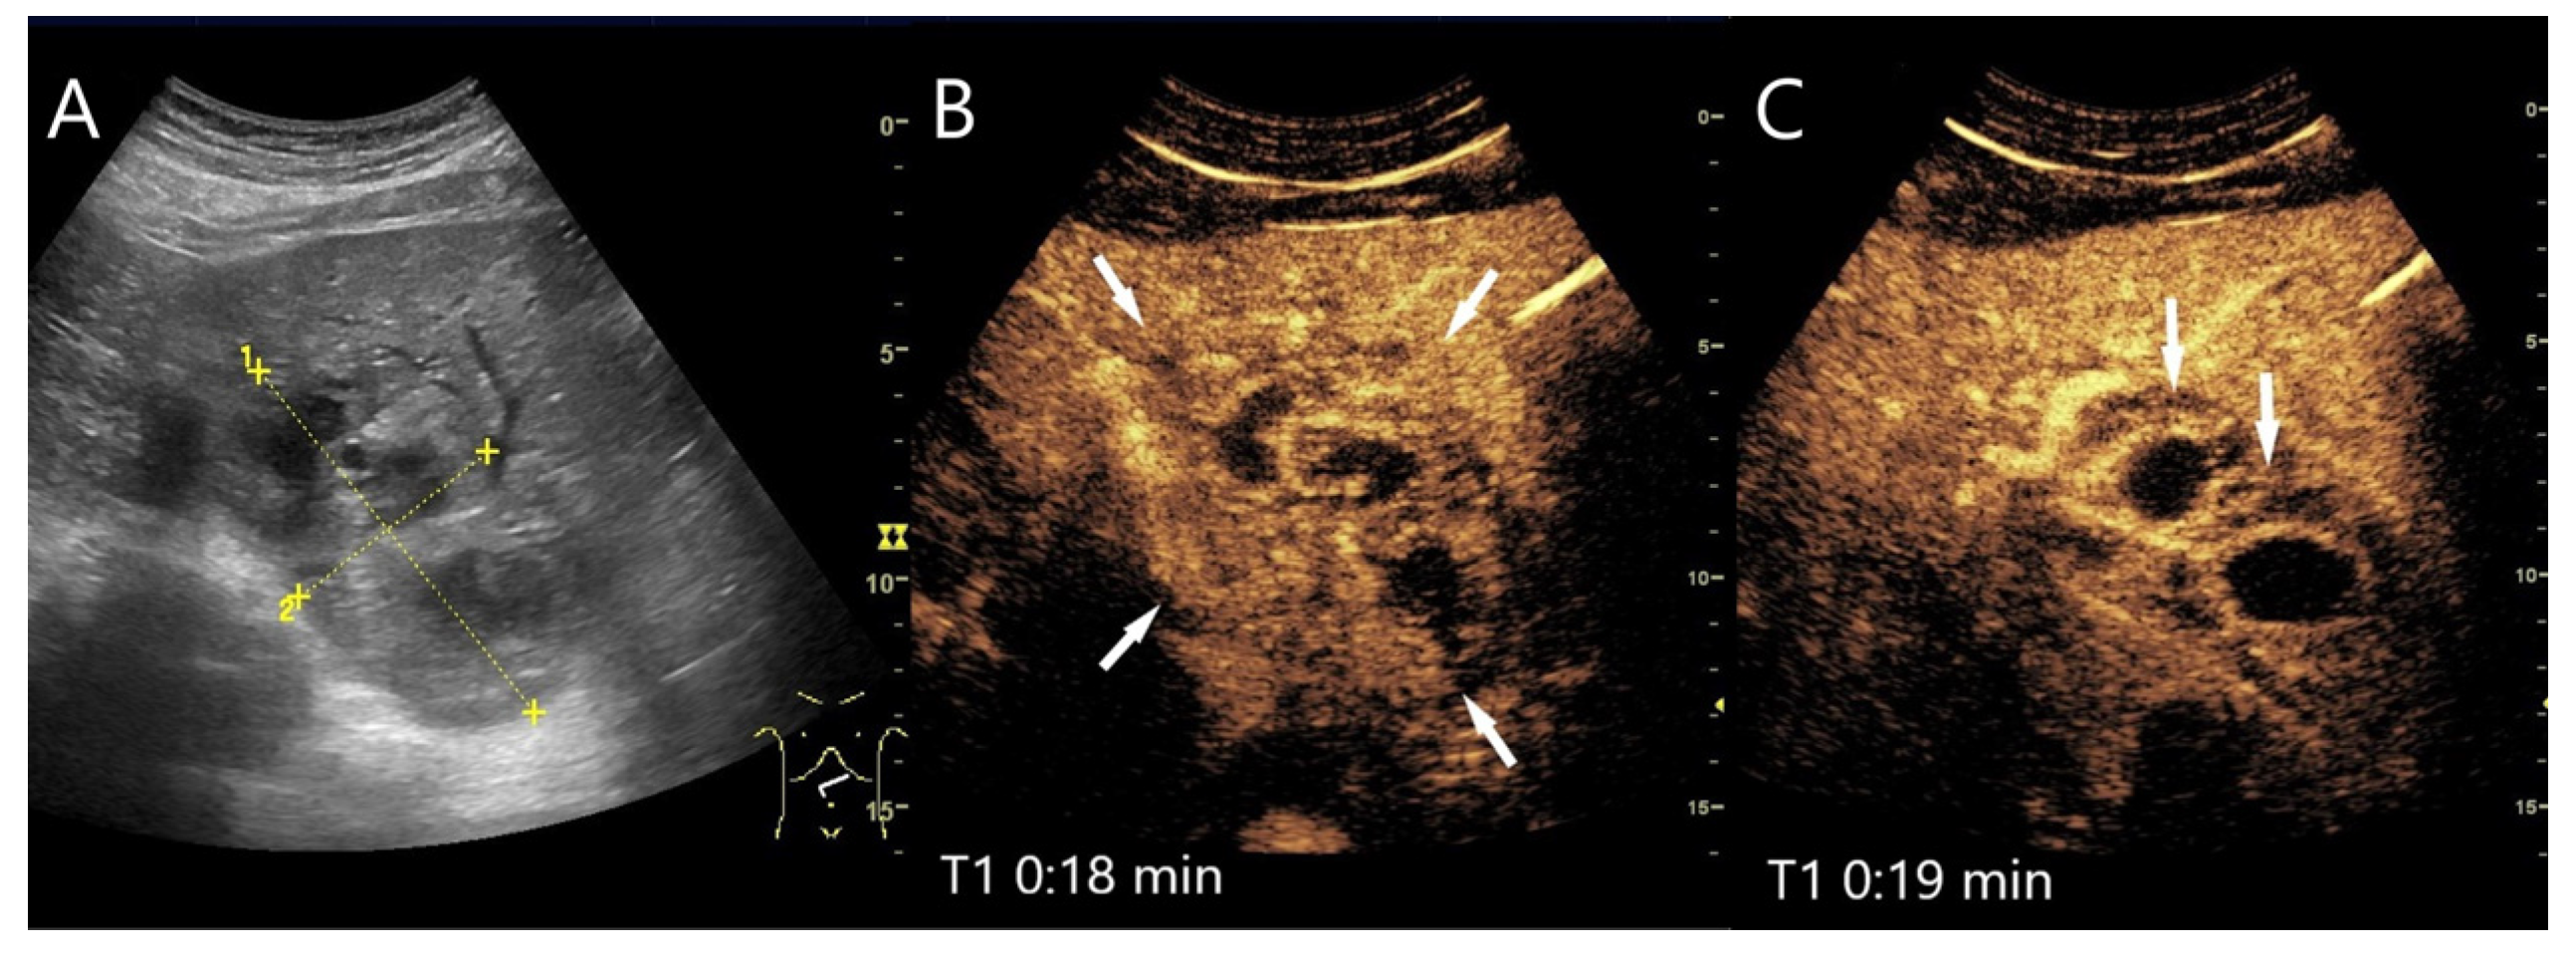

Figure 6.

Inflammatory hepatocellular adenoma. Large mass (between the arrows) in the right lobe of the liver in a male patient (A). In the AP, the lesion shows a diffuse reticular enhancement (B), then a homogeneous hyperenhancement (C). In the PVP at 1:35 min, a shallow washout begins (D), which continues progressively in the LP (E,F). Histology after surgical resection confirmed the HCA.